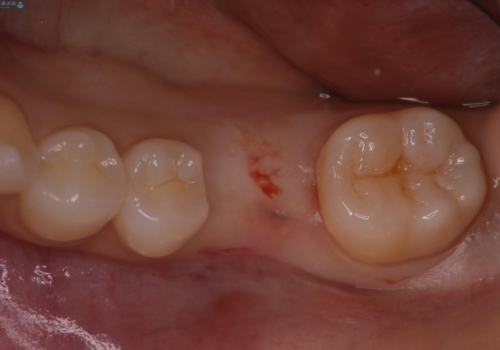

- 他院で抜歯と言われ、今後どうしたらいいのかを相談された患者様です。

抜歯を行った後は、Br、義歯、インプラント、何もしないという選択肢のメリットデメリットを説明させていただき患者様がインプラント治療を希望されたので今回治療させていただくことになりました。

歯のなかったところをインプラント治療を行うことによってまた噛める喜びを感じていただけて良かったと思っております。